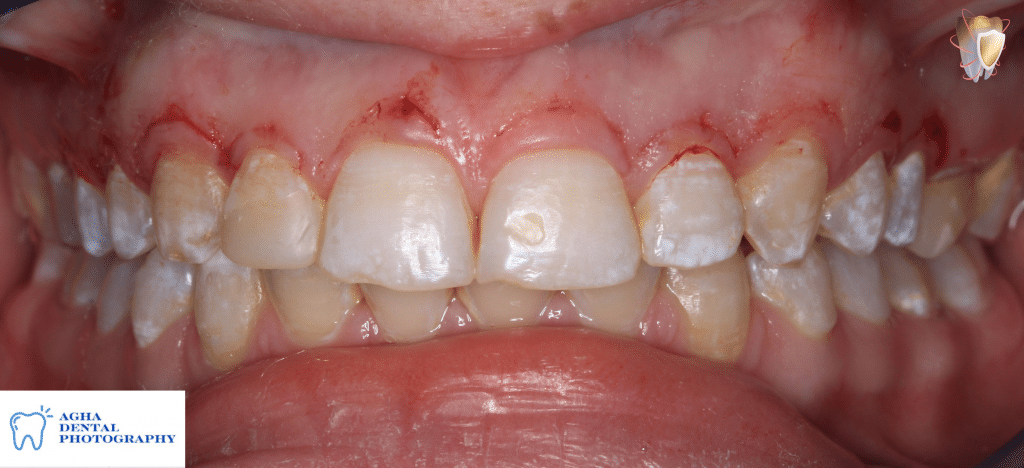

Intra oral photo showing altered passive eruption & disharmony of gingival margins with each other

Determining Zenith points guided by probing depths from left 2nd premolar to right 2nd premolar

"Note that zenith points of centrals, canines, 1st & 2nd premolars bilaterally should be in a same imaginary line while those of laterals should be 1mm coronal

Drawing incision lines to easily demarcate

the excised tissues